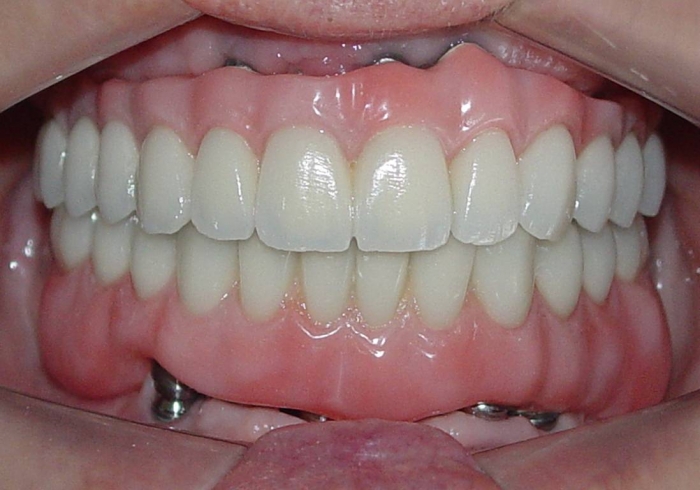

Próteses fixas em porcelana sobre implantes

Sorriso do caso finalizado em maio de 2012